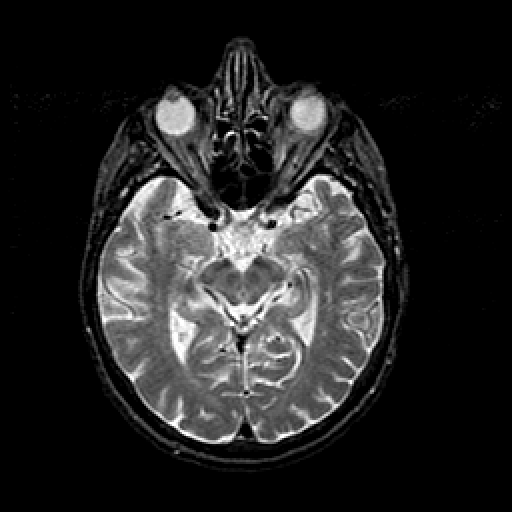

T2-weighted structural MR: Slice 23

Slice 23